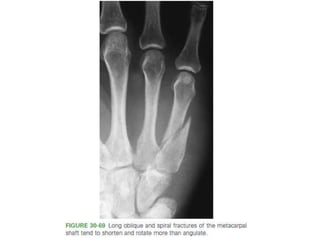

METACARPAL FRACTURES- INTRODUCTION

• Fracture patterns - head, neck, and shaft.

• Transverse Neck and shaft fractures - apex dorsal angulation.

• normal anatomic neck to shaft angle of 15 degrees.

• Evaluation of rotation .

• Ten degrees of malrotation ( 2 cm of overlap at the digital tip)

is the upper tolerable limit.

• #109 Long oblique spiral fracture.